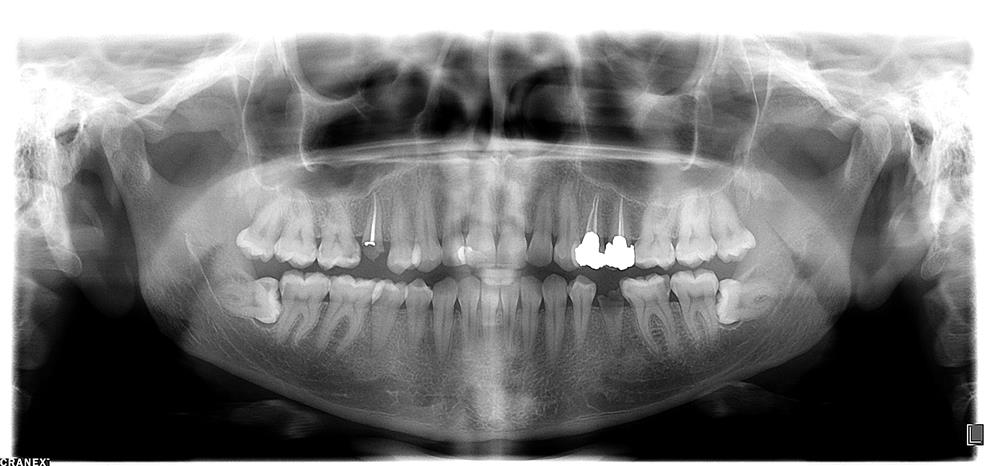

عکس پانورامیک دندان (اصطلاحا OPG)  چیست ؟

رادیوگرافی پانورکس یا رادیوگرافی پانورامیک یکی از مرسوم ترین رادیوگرافی های تشخیصی در دندانپزشکی است.در این نوع رادیوگرا...

نقاط ضعف تصاویر پانورامیک

دو مورد از نقاط ضعف تصاویر پانورامیک عبارتند از: 1-وضوح و رزولوشن کمتر نسبت به تصاویر داخل دهان 2-ایجاد اورلب  در تص...